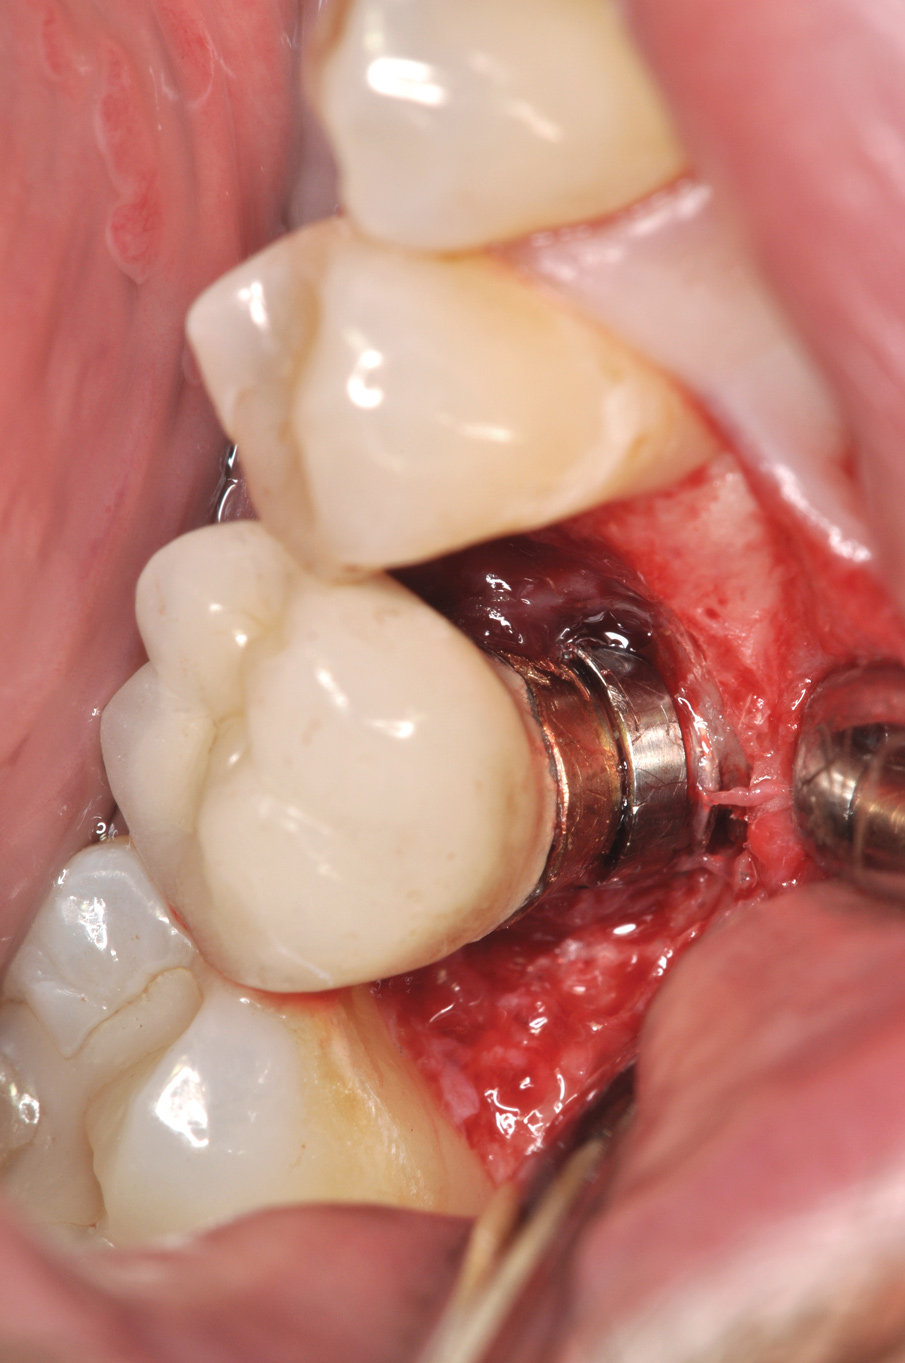

Fig 8. Loss of restoration and subsequent tissue overgrowth from broken abutment screw as shown in the radiograph (Fig 9).

Figure 8

Fig 9. Radiograph depicting fractured screw inside of the implant.

Figure 9